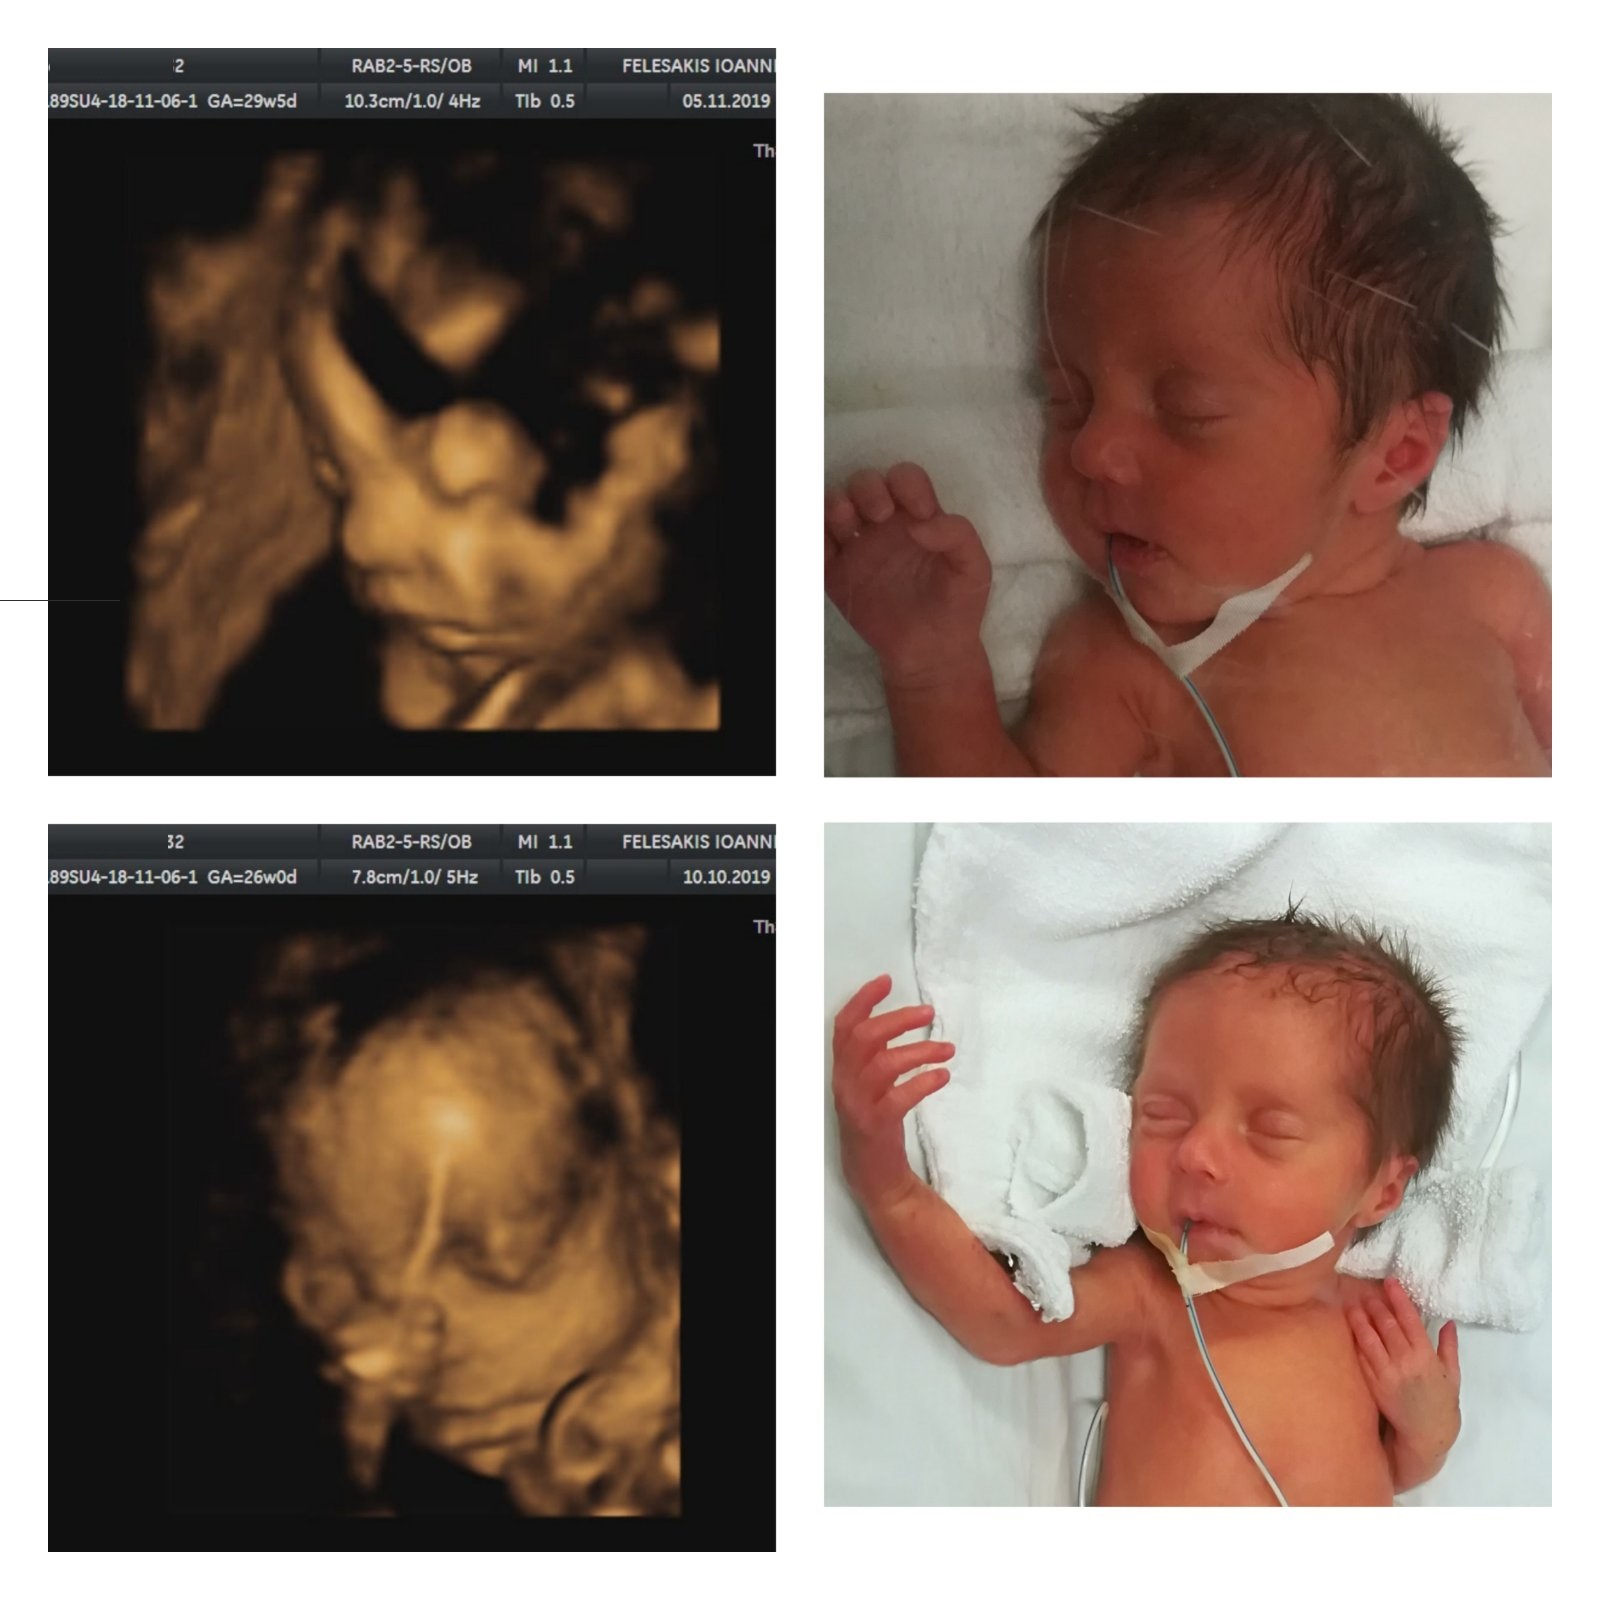

Είναι μία εντυπωσιακή απεικόνιση του εμβρύου μέσα στο "δικό του χώρο". Υπάρχει η δυνατότητα στατικής απεικόνισης όσο και "realtime".Τα αποτελέσματα απεικονίζονται σε ψηφιακή μορφή και αποτελούν επί της ουσίας τη πρώτη οπτική επαφή του ζευγαριού με το έμβρυο.

Στην πραγματικότητα η χρήση του είναι να επιβεβαιώσει μία ανωμαλία η οποία ανιχνεύεται με τη δισδιάστατη υπερηχογραφία.